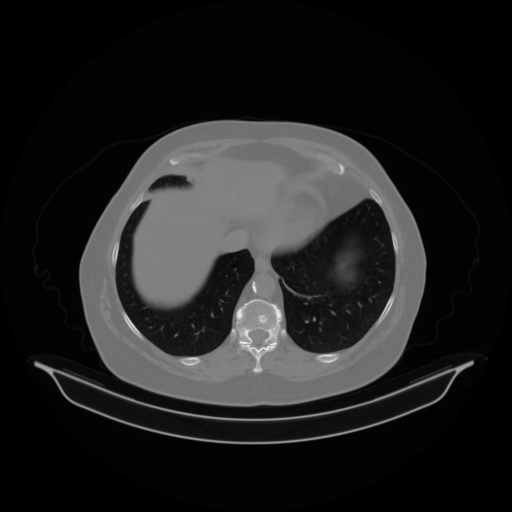

Image Grid

4Γ—3 grid: Rows show different image types (Original NATIVE, Reconstructed NATIVE, Original VENOUS, Generated VENOUS), Columns show windowing techniques (No Window, Lung Window, Mediastinum Window)

Original VENOUS CT scan

Mediastinum window (WL 40, WW 400 β†’ Low βˆ’160, High +240)